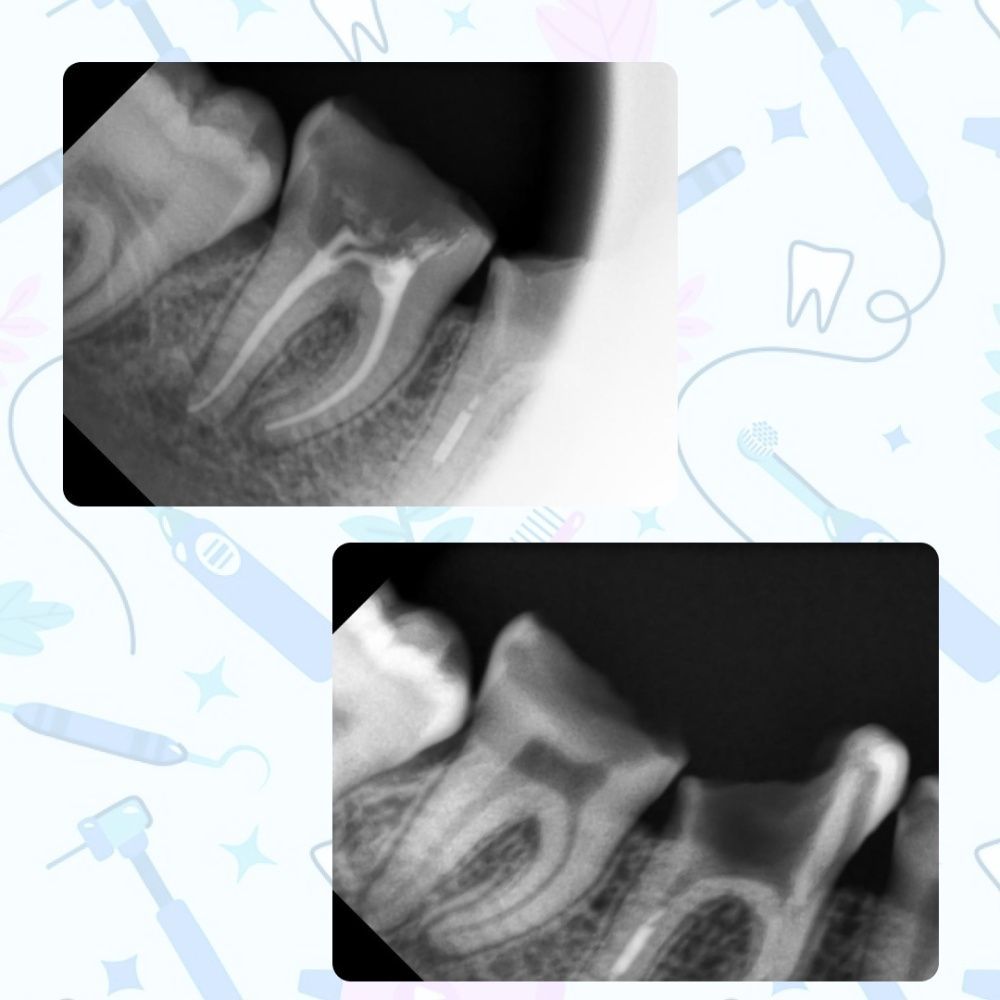

В результате осмотра и диагностики была обнаружена обширная кариозная полость в жевательном зубе и воспаление зубной ткани (пульпит). Проведено эндолечение зуба за одно посещение. Работа выполнена врачом-стоматологом-терапевтом высшей категории Мурзабаевой Г.А.

Данный клинический случай описывает рядовую ситуацию, с которой стоматолог сталкивается достаточно часто. Стоит отметить, что пульпит — это осложнение одного из наиболее распространённых заболеваний твёрдых тканей зуба — кариеса. Диагностирование кариеса на ранних этапах является одним из ключевых способов профилактики пульпита.